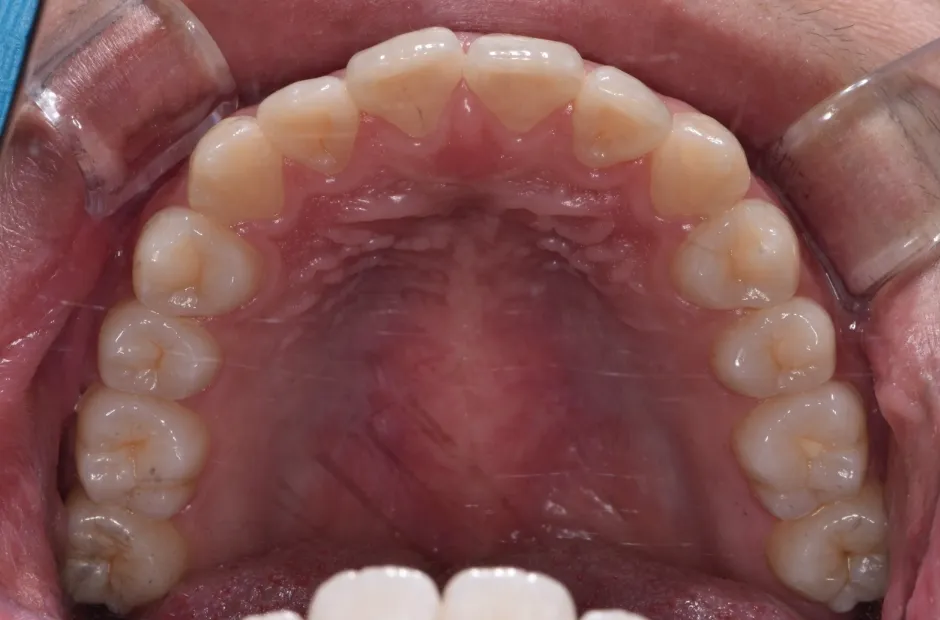

叢生

| 診断名・主訴 | 叢生 |

|---|---|

| 年齢・性別 | 43歳・女性 |

| 治療期間・回数 | 2年7か月 27回 |

| 治療に用いた主な装置 | 舌側矯正 |

| 抜歯部位 | 両顎4,4 |

| 治療費 | 100万円(税抜) |

| リスク・副作用 | 装置による違和感・疼痛・歯肉退縮・歯根吸収・虫歯のリスクなど |

治療前